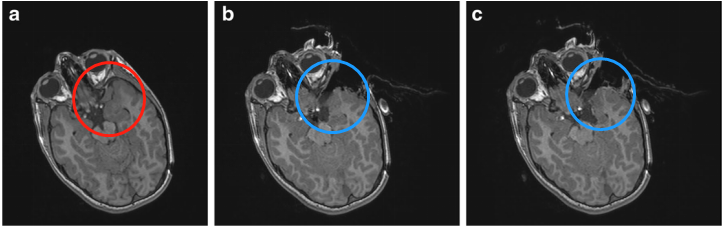

一个8岁男孩曾有全身性癫痫发作、进行性亢进和说话能力受损,大脑MR显示他“左颞叶损伤”(下图a),后在术中神经导航和术中磁共振成像(iMRI)系统的帮助下经左颅骨开颅手术治疗,术中,病变边缘很难与正常组织区分开。在被评估为可全切的肿瘤后,进行了术中MRI检查,结果显示在颞后肌膜区域残留了肿瘤(下图b)。然后使用更新后的导航图像继续进行手术,并如二个术中MRI对照所示将肿瘤全切(下图c)。术后状态平稳,组织学结果显示神经节神经胶质瘤(WHO 1级)。在为期1年的随访中,无肿瘤复发,且无癫痫发作。

图:a为左颞神经节神经胶质瘤(WHO I级)的术前MRI。b为术中MRI控制显示在颞后肌膜区域残留肿瘤。c继续手术,术中二次MRI显示病变已全切